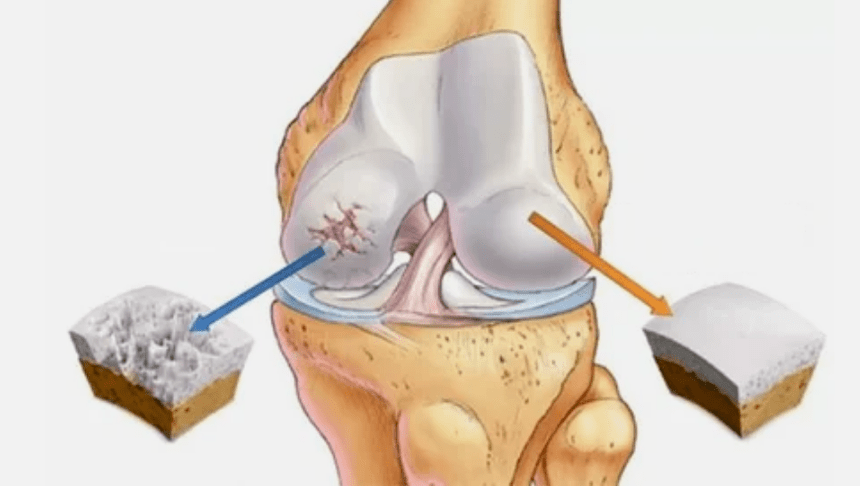

- The primary injury affects the cartilage IALINA.In case of circulatory disorders, a deterioration of pathological power occurs.It is the first step or cause, which can occur arthrosis.

- IALINA coating pathologies.The thinning of the cartilage leads to the replacement of its pathological tissues - bone structures.

- The anomalous growths appear on cartilage - osteophytes.

- The violation of the drift of the natural anatomy of cartilage and bones causes the overload of healthy cartilage areas.The destruction of joint tissues without treatment is constantly progressing and leads to disability.

When the degree of disease increases, pathological processes are still aggravated.In the end, the whole cartilage IALINA is destroyed.